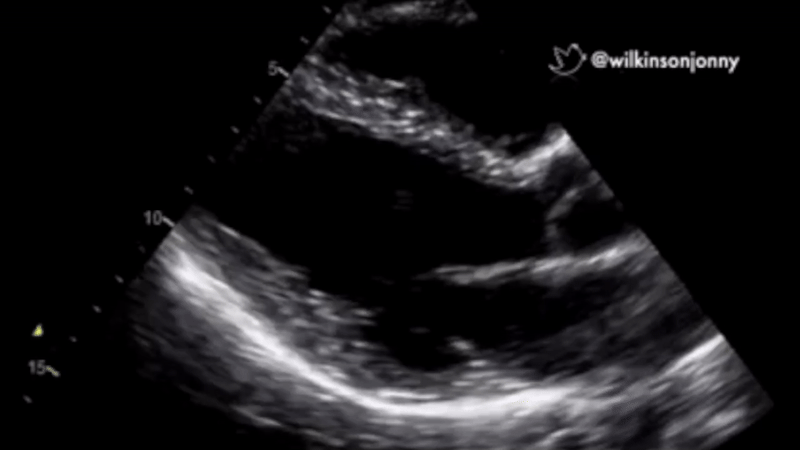

At Cauchy Analytics, we transform medical care through real-time echocardiography and continuous hemodynamic monitoring.

Leveraging advanced analytics and AI, our non-invasive solutions empower clinicians with immediate, data-driven insights - minimizing risks and improving patient outcomes.

By integrating seamlessly into ICU, emergency, and perioperative workflows, we enable faster interventions and more precise decision-making when every second counts.